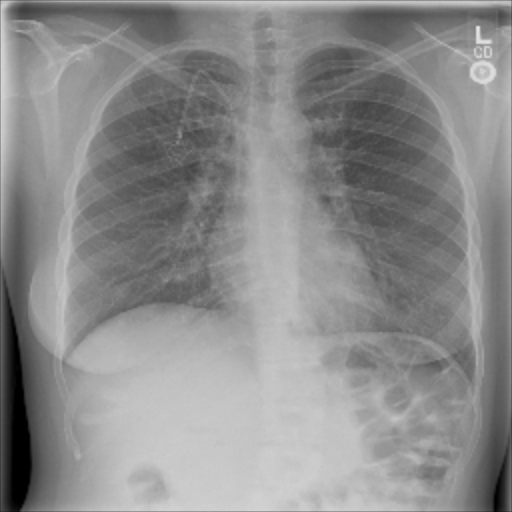

Pneumothorax is a lung pathology that is associated with abnormal collection of air in the pleural space between the lung and the chest wall. It can result from a variety of etiologies including chest trauma, pulmonary disease, and spontaneously. Pneumothorax can be life-threatening and is considered an emergency in intensive care, requiring prompt recognition and intervention [12].

The data used in the following experiments consists of DICOM X-ray images, obtained from the University of Washington Medical Center and affiliated institutions, centered in Seattle by scanning radiology reports from the last three years. Inclusion criteria were: (i) Digital Radiography (DR) images, (ii) Chest radiographs, (iii) Posterior-anterior or anterior-posterior view position, (iv) Adult patients. Any personal health information was removed. Image-level labels were derived from natural-language processing based analysis of the reports. Cases were partially reviewed by a radiologist to confirm appropriate finding in the report’s impression section and this represented a critical finding. The resulting dataset contained 1003 images: 437 with pneumothorax, 566 with a different or no abnormality detected. We generated pixel-level annotations of the pneumothorax region for 305 of the positive cases. For training and evaluation, we divided the dataset into five cross-validation splits of similar size, such that images of the same patient resided in the same split.